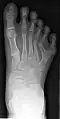

Полидактили́я (др.-греч. πολύς — много + δάκτυλος — палец, синоним — многопалость), также известная как гипердактилия — анатомическое отклонение, характеризующееся бо́льшим, чем в норме, количеством пальцев на руках или ногах у человека, собак, котов и лошадей. Противоположным отклонением является олигодактилия.

У людей и животных она может проявляться как на одной, так и на обеих руках. Обычно дополнительный палец представляет собой небольшой кусочек мягкой ткани, которую можно удалить. Иногда это просто кость без суставов; очень редко лишний палец бывает полноценным. Дополнительный палец чаще всего образуется со стороны мизинца, реже на стороне большого пальца и очень редко между средними пальцами. Обычно лишний палец является аномальным разветвлением обычного пальца, редко возникает на запястье, как обычный палец.